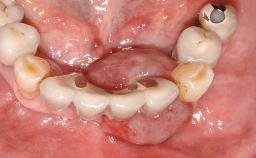

The fracture of an implant after it has been restored is one of the most severe complications. It most frequently occurs in partially edentulous jaws (1.5%). Most implant fractures involve implants with a diameter of 3.75 mm made of commercially pure titanium (Eckert 2010). Unfortunately, many cases are not reported or documented by the clinicians involved in resolving the problems created by the fracture. This case report describes the management of an implant fracture at site 36 in a middle-aged male patient. The implant had been restored with a screw-retained metal-ceramic crown.

Case Type Single-Tooth Space

Jaw Mandible

Area Posterior

# of Teeth 1

# of Implants 1